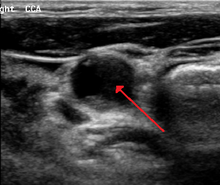

Carotid stenosis is usually diagnosed by color flow duplex ultrasound scan of the carotid arteries in the neck. This involves no radiation, no needles and no contrast agents that may cause allergic reactions. This test has moderate sensitivity and specificity, and yields many false-positive results.

Typically duplex ultrasound scan is the only investigation required for decision making in carotid stenosis as it is widely available and rapidly performed. However, further imaging can be required if the stenosis is not near the bifurcation of the carotid artery.